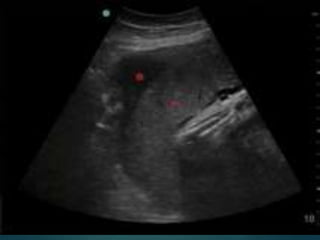

El desprendimiento prematuro de placenta normoinserta es la separación de la placenta de su sitio normal de implantación antes del nacimiento del feto, ocurre en el 30% de los casos de sangrado en el tercer trimestre. Puede presentarse con hemorragia externa visible o hemorragia oculta interna, siendo esta última forma más grave con mayor riesgo de complicaciones como coagulopatía y muerte fetal. El tratamiento consiste en reposo absoluto, monitoreo continuo y control del sangrado a través de ecografía y transfusión si es neces